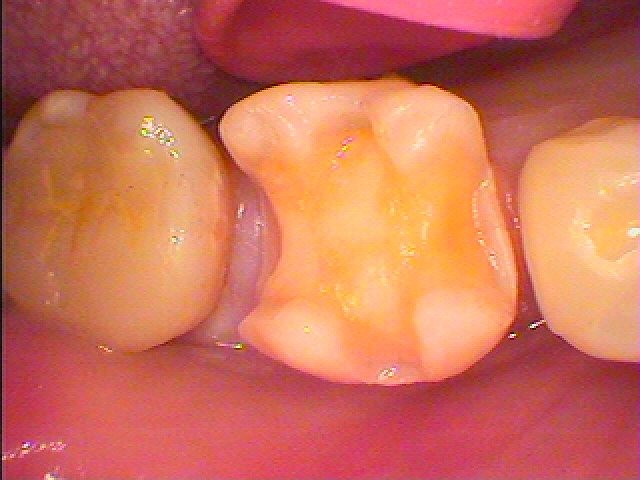

セラミックによる審美治療。 虫歯治療。 綺麗な白い歯を求めて| |広島市安佐南区の歯科医院 セラミックによる審美治療。 虫歯治療。 綺麗な白い歯を求めて トップ お知らせ・ブログ セラミックによる審美治療。 虫歯治療。 綺麗な白い歯を求めて セラミックによる審美治療。 虫歯治療。 綺麗な白い歯を求めて Web診療予約 初めての方へ 選ばれ続ける理由 院内設備について 歯が痛いしみる一般歯科 歯がぐらぐらする歯周病 健康な歯を保ちたい予防歯科 子供の虫歯予防をしたい小児歯科 銀歯をセラミックに審美歯科 白い歯を目指しませんか?ホワイトニング 矯正専門医がいるので安心矯正歯科 抜けた歯を補いたいインプラント・入れ歯 医院案内 スタッフ紹介 メリィハウス歯科クリニックオフィシャルホームページ ラベンダー歯科クリニックオフィシャルホームページ お知らせ・ブログ ホーム 診療科目 一般歯科 歯周病治療 予防治療 小児歯科 審美治療 ホワイトニング 矯正歯科 入れ歯・インプラント マウスピース矯正 初めての方へ 院長・スタッフ 設備紹介 医院案内・アクセス メニューを閉じる